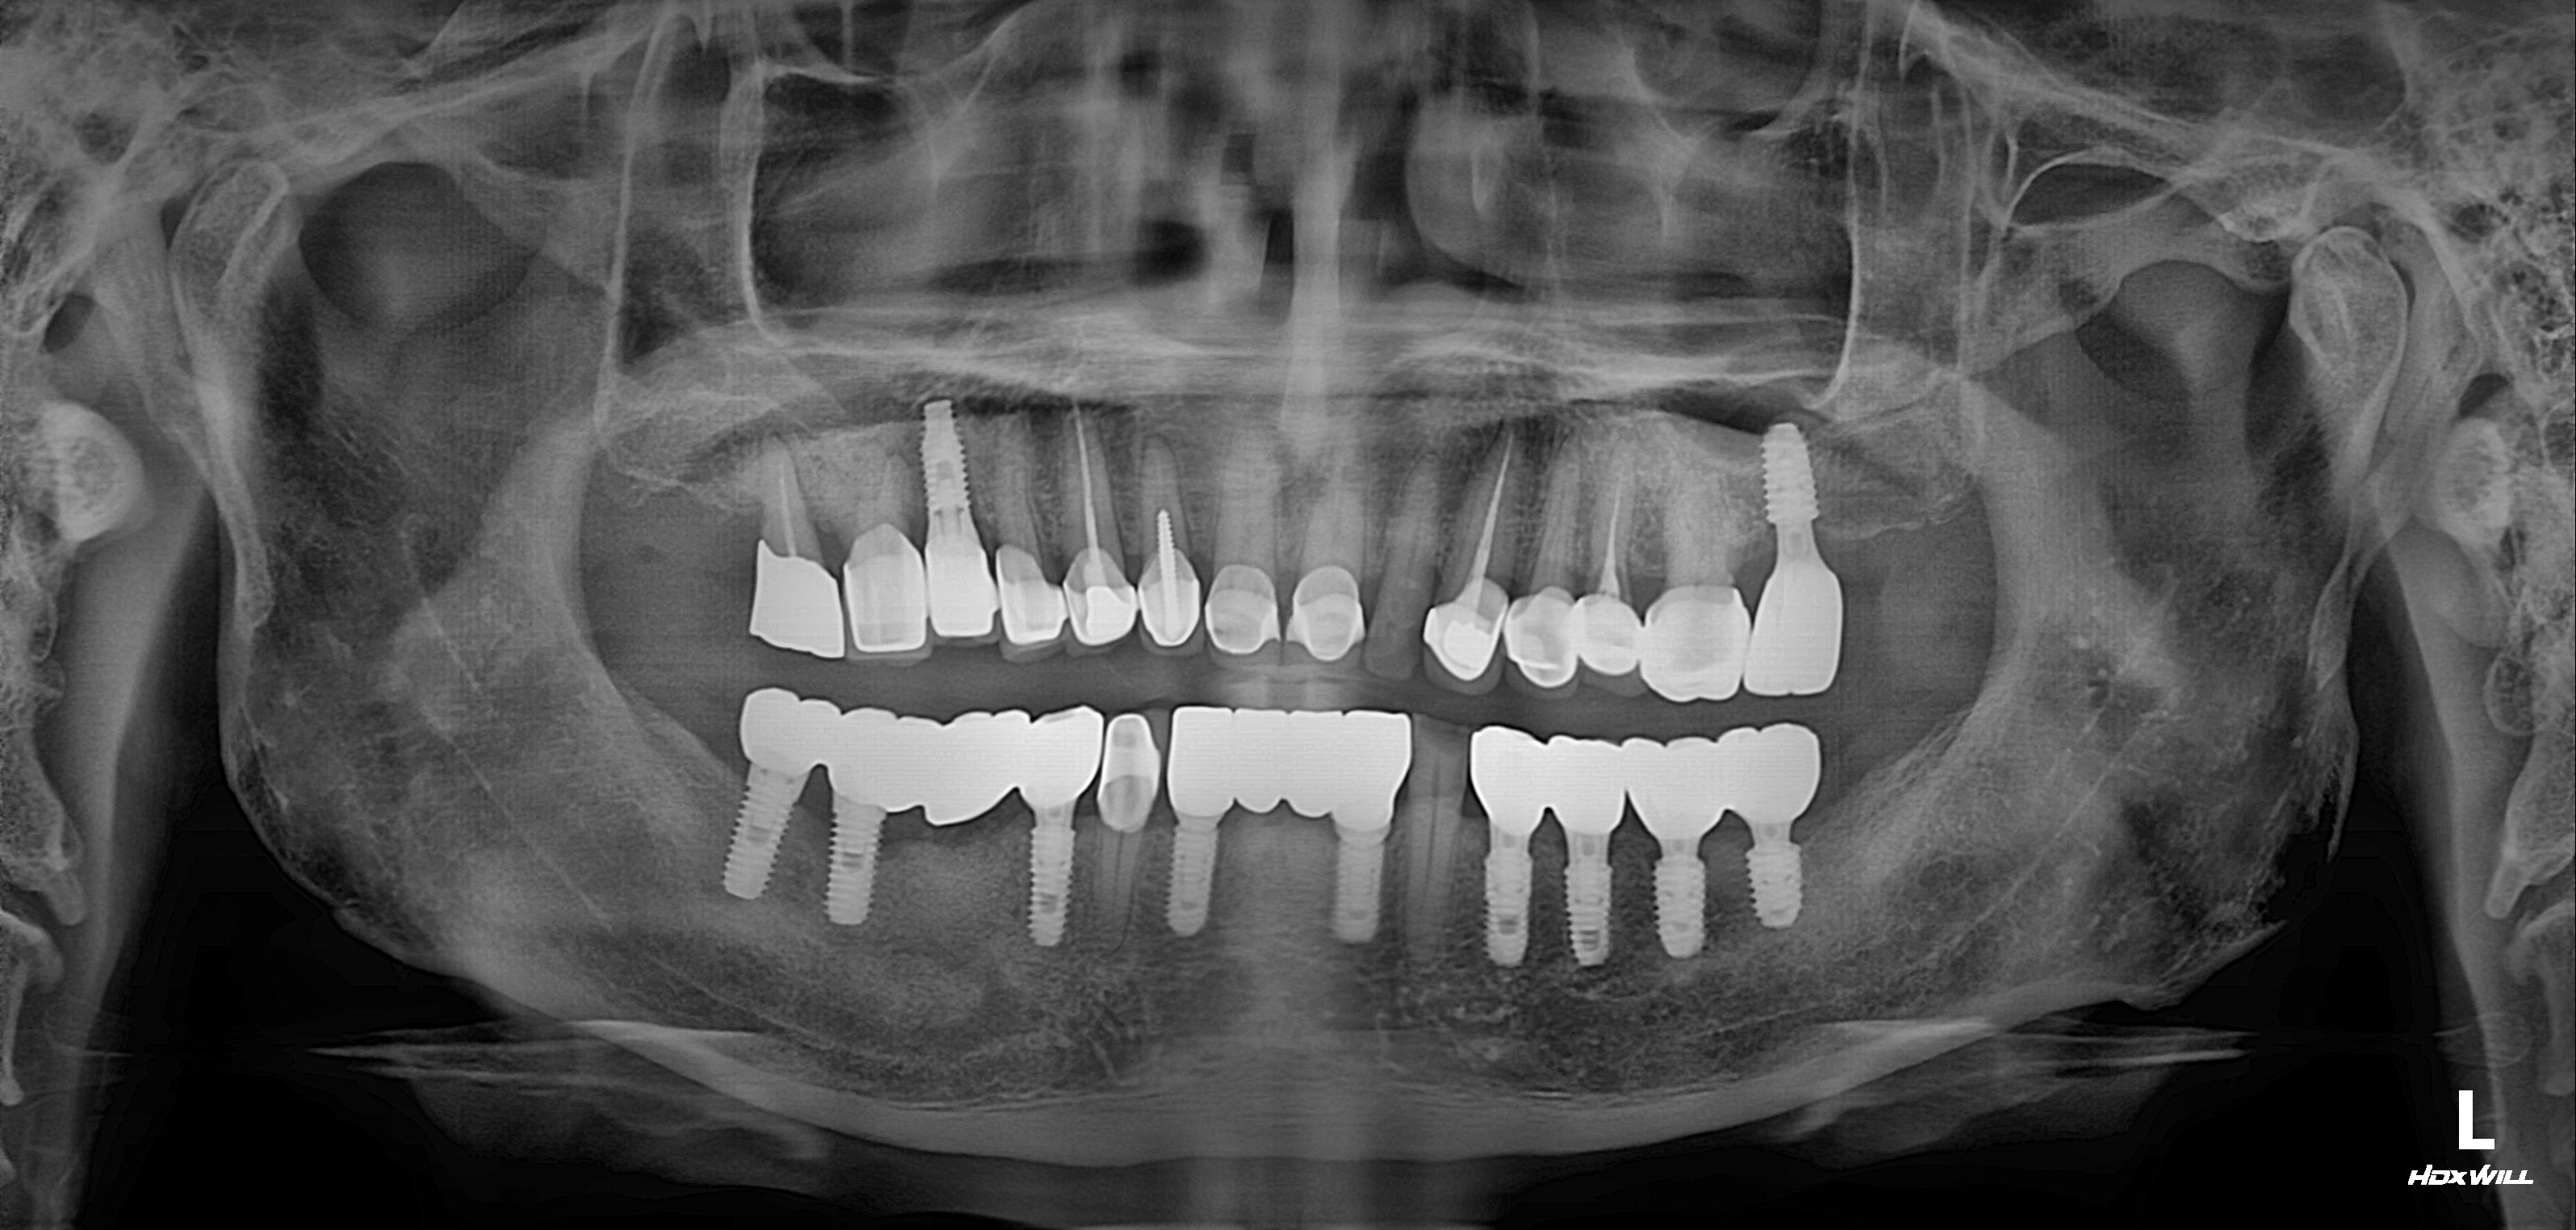

전치부+구치부 임플란트 식립사례

전후사진

수술 전

수술 후